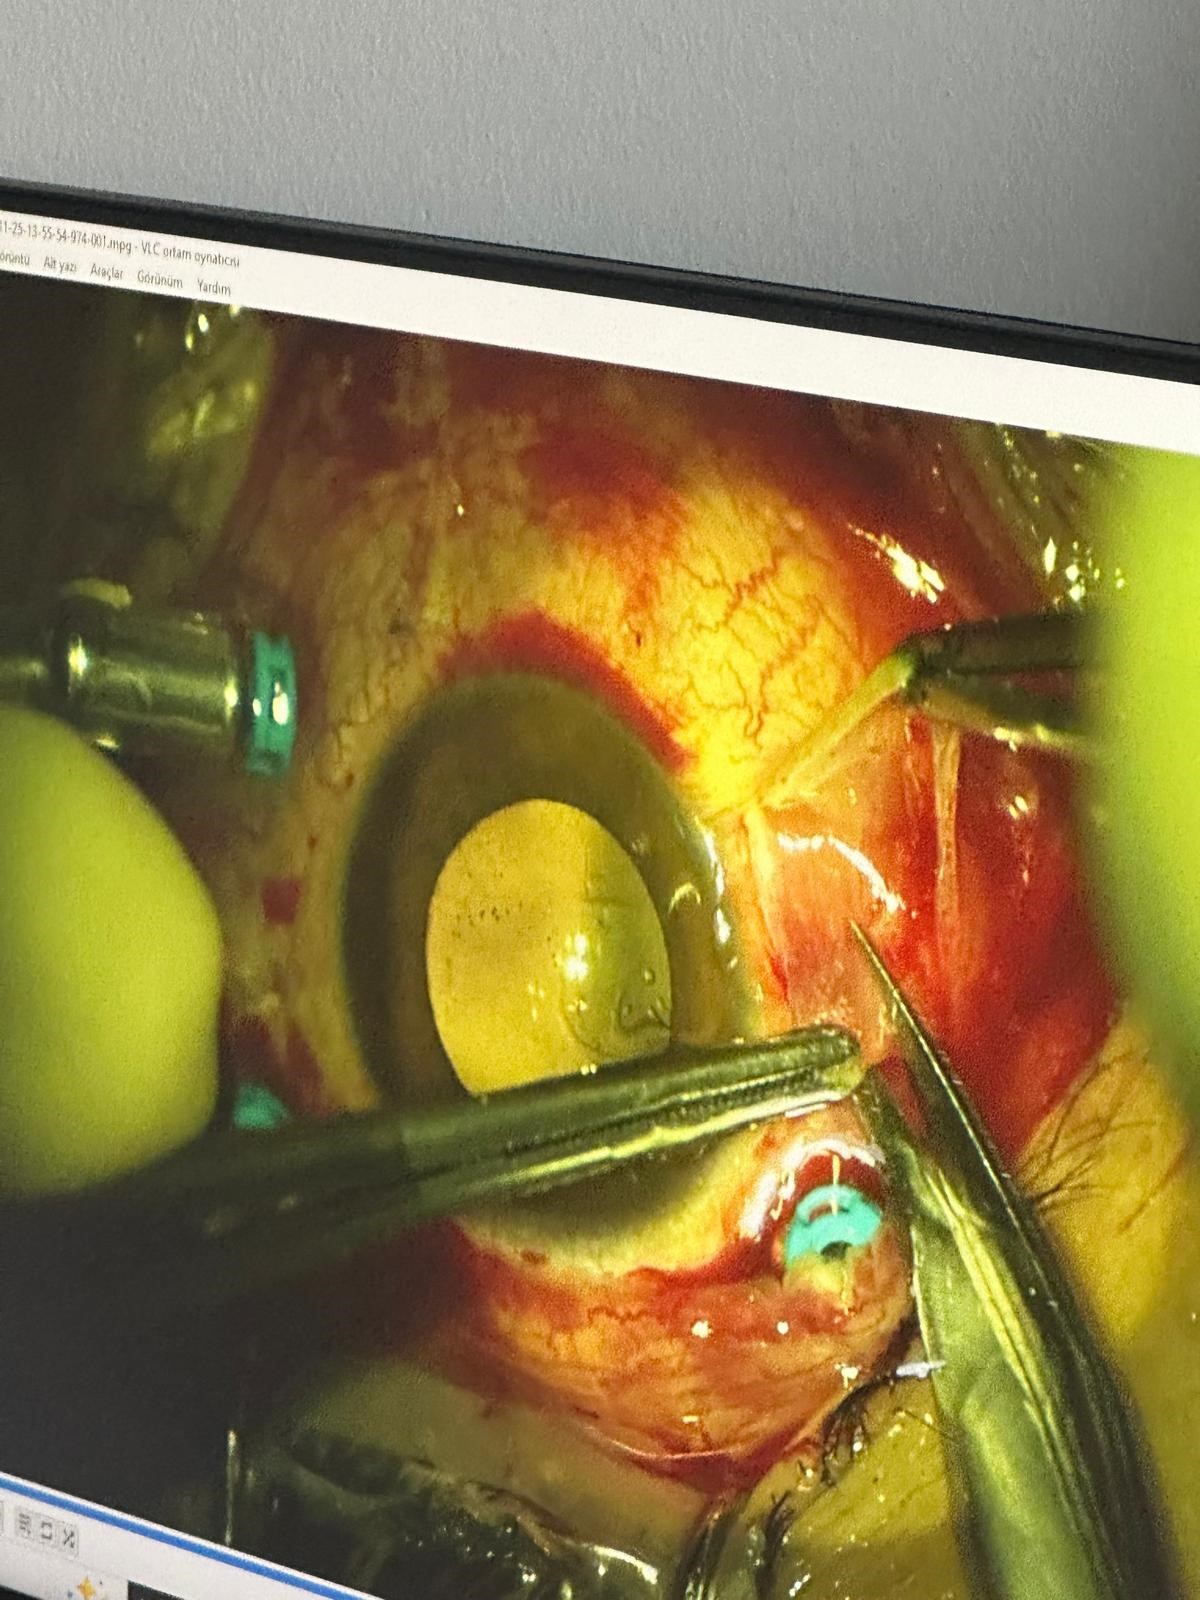

"Müvekkilim ile eşi bir süredir ayrı yaşıyor. Müvekkilim, eşinin talebi üzerine evde unuttuğu özel eşyayı kayınpederinin evine götürüyor. Aracında eşini beklerken kayınpederi elindeki tüfekle araca ateş ediyor. Saçmalar hem araca hem müvekkilime isabet ediyor. Şu ana kadar dört operasyon geçirmesine rağmen görmesinde bir iyileşme sağlanamadı. Göz nakli gerekebilir. Araçta yaklaşık 20 saçma izi var. Müvekkilimin gözünde, kulağında ve başında saçmalar bulunuyor."